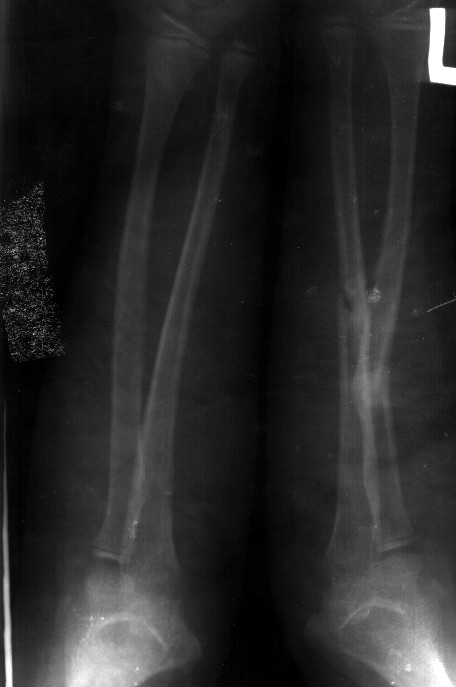

Сделал симметричные снимки с максимальной супинацией и пронацией при согнутом предплечье в 90 град. Объем ротационных движений 90-100 град.

Снимок один сделан с супинацией, второй - оба предплечья в одинаково нейтральном положении. то есть по этим снимкам объем ротационных движений не оценить. Снимко в двух проекциях лучше и делать в среднем положении между пронацией и супинацией, то есть обе проекции в однм и том же положении, когда линия, проходящая через шиловидные отростки, идет в плоскости головки. Прошу прощения за усложнение простых вещей.